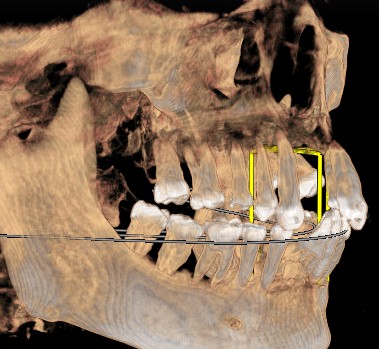

患者女,五十岁,近几年出现刷牙出血和牙齿的松动,甚至部分脱落,近期前来我院就诊。患者全身健康,否认糖尿病,否认家族病史。临床检查:口腔卫生差,可见大量菌斑,软垢。牙石+++,牙龈暗红。根面暴露,前牙部分脱落。X线示牙槽骨吸收至根尖1/3。

治疗计划:1拔除无法保留的牙齿。2牙槽骨吸收至根尖2/3以上的患牙进行根管治疗。3分次进行牙周刮治。4缺失牙修复。5定期维护